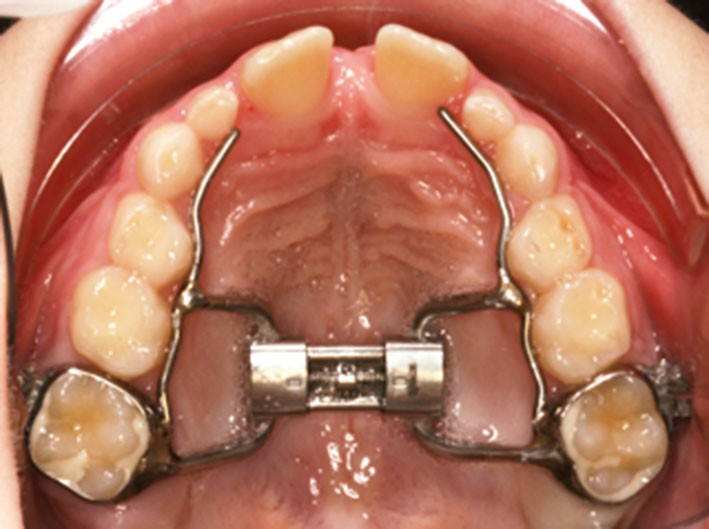

Disjonction intermaxillaire ou distraction maxillaire rapide (DMR)

Dans les années 1960-1970, des orthodontistes, sans connaissance particulière sur le sommeil, avaient déjà rapporté des résultats cliniques positifs lors de parasomnies, en utilisant la distraction maxillaire rapide (DMR) (fig. 3), et démontré l’effet sur les résistances nasales. Les mécanismes par lesquels la DMR entraîne une formation d’os au niveau de la suture palatine, l’élargissant lors de la traction, ont été bien étudiés.

Cette technique s’est montrée très efficace chez le jeune enfant au palais dur étroit et ogival. En trois semaines, avec une expansion en moyenne de 0,25 à 0,50 mm par jour, une nouvelle formation d’os est observée, avec un effet clinique démontré sur la respiration lors du sommeil par PSG. Cette approche a plusieurs avantages, donnant non seulement plus de place au pharynx, mais surtout diminuant considérablement la résistance nasale anormale lors du sommeil. Elle permet aussi de réduire l’impact d’une déviation septale marquée, sans avoir recours à une intervention chirurgicale. En effet, le septum nasal est reconnu comme facteur de croissance crânio-faciale, et une intervention septale chez un enfant prépubertaire, difficile, avec un résultat à long terme souvent médiocre, pourrait affecter la croissance faciale. La DMR peut être réalisée au cours de la croissance de l’enfant jusqu’à ce que l’ossification complète de la suture palatine soit atteinte (entre 14 et 17 ans selon l’enfant). Mais cette intervention orthodontique a des limites : il n’existe pas de cartilage mandibulaire et la distraction du maxillaire est ainsi limitée dans son efficacité.